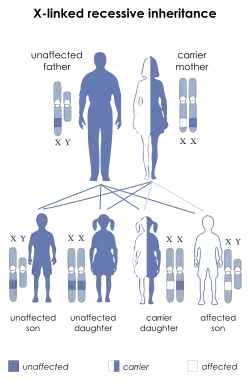

L1 syndrome is a group of mild to severe X-linked recessive disorders that share a common genetic basis. The spectrum of L1 syndrome disorders includes X-linked complicated corpus callosum dysgenesis, spastic paraplegia 1, MASA syndrome, and X-linked hydrocephalus with stenosis of the aqueduct of Sylvius (HSAS).[1][2] It is also called L1CAM syndrome (for the disorder's causative gene) and CRASH syndrome, an acronym for its primary clinical features: corpus callosum hypoplasia, retardation (intellectual disability), adducted thumbs, spasticity, and hydrocephalus.[2]

There are various types of genetic testing that can be used to confirm an L1 syndrome diagnosis in a patient.[2] After birth, genetic tests carry a low-risk of physical complications and are minimally-painful: for the patient, the process requires a small amount of blood being drawn from the arm using a needle.[32] However, prenatal genetic testing carries significant risks for both the fetus and mother due to the need to remove genetic material from the fetus while it is still in utero.[33] In order to conduct prenatal genetic testing, the mother and fetus must undergo either amniocentesis (the surgical puncturing of the amniotic sac, which holds the fetus in the womb) or, less frequently, chorionic villus sampling.[34] Amniocentesis provides a sample of amniotic fluid that can be used to screen for sequence variants or chromosomal variants,[35] whereas samples obtained through chorionic villus sampling can only be used to detect major chromosomal abnormalities (such as trisomy 21),[36] making chorionic villous sampling less relevant in the context of diagnosing L1 syndrome (which is often caused by sequence variants).[37] Amniocentesis (typically performed between 15 and 18 weeks of pregnancy) has a 1% risk of complications for mother and fetus, including miscarriage, while chorionic villus sampling (typically performed between 10 and 12 weeks of pregnancy) has a 2% risk of complications including miscarriage.[33] Mothers carrying a fetus with suspected L1 syndrome will often elect to undergo amniocentesis despite its risk, rather than waiting to pursue lower-risk genetic testing after their child is born, because prenatal diagnostic results can inform considerations to terminate the pregnancy.[38][39]